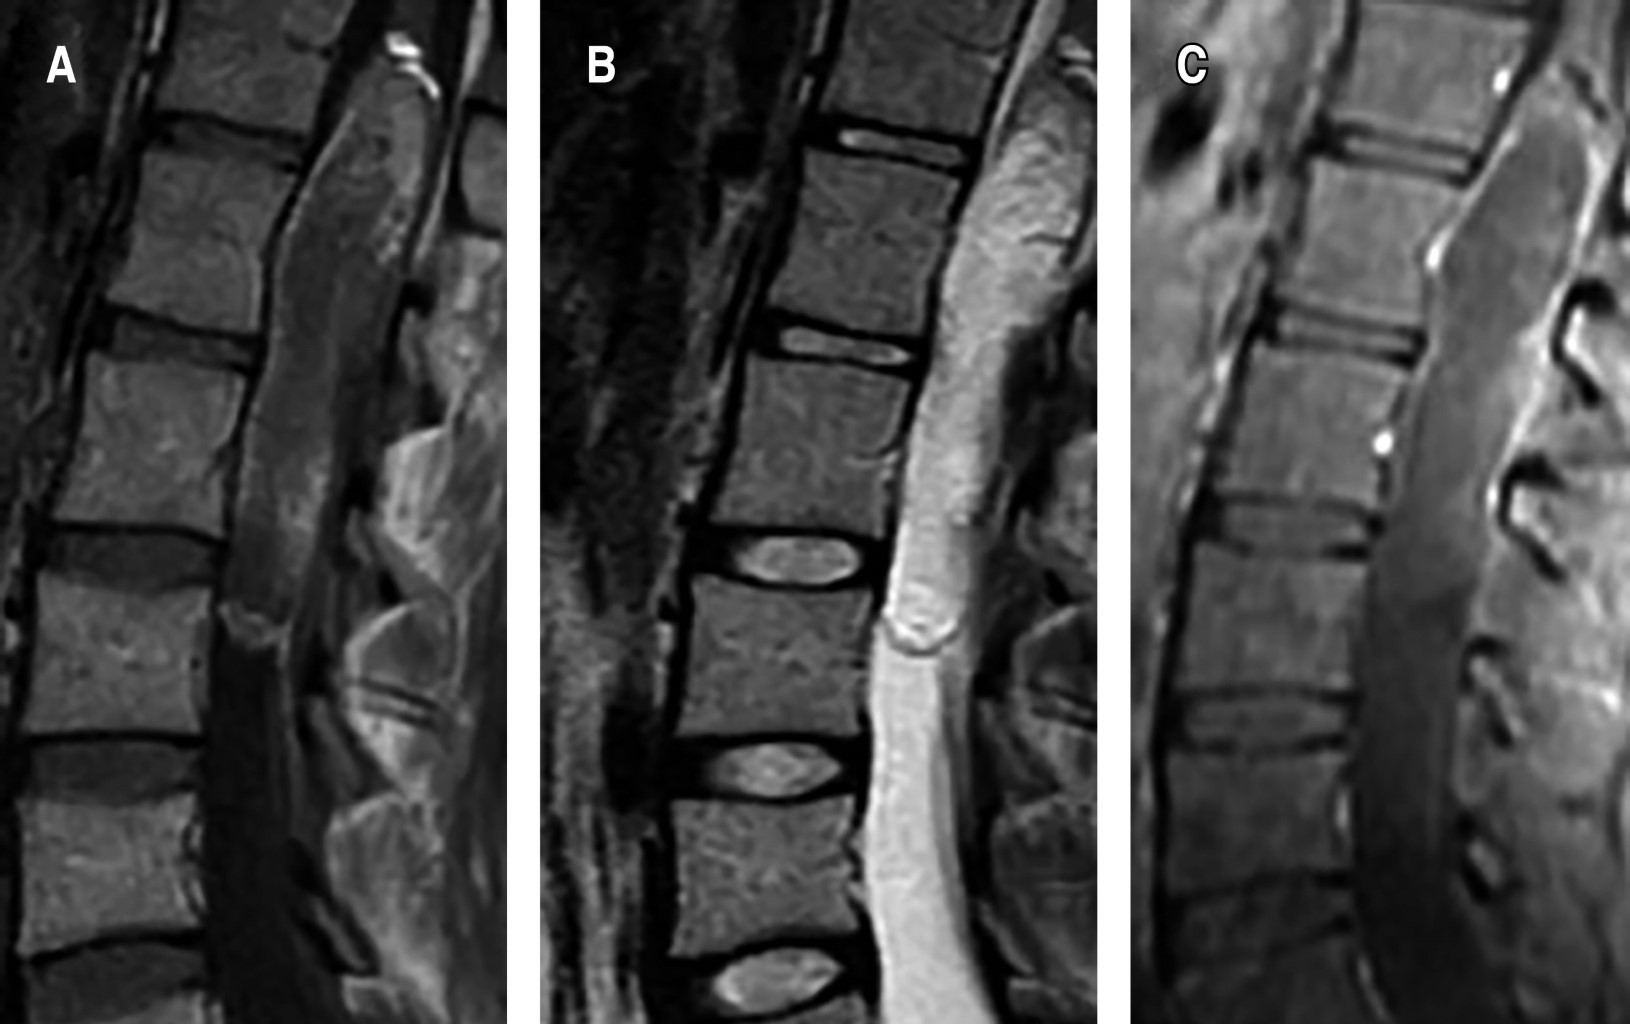

Female patient, 26 years old, with a history of pain in the right pelvic member of six years of evolution, with progressive claudication, repeated urinary tract infections, emergency urinary incontinence, admission to the emergency service, with an incidentally finding an intramedullary cyst from the vertebral body T12 to L3, with heterogeneous enhancement with intravenous contrast (Figure 1). Surgical resection was performed with neuro monitoring and posterior approach, laminectomy of L1 and L2, with the finding of an intradural extramedullary encapsulated macroscopically with pearled appearance, dismissable consistency, and easily resectable. Satisfactory macroscopic resection was performed, leaving a small remnant attached to the medullar cone (Figure 2). The histopathological report of the lesion was abundant keratin, compatible with a dermoid cyst (Figure 3). The patient left the hospital two days after the procedure, without sensory or motor deficit in the lower limbs, in follow-up at 2 weeks showed improvement in urinary incontinence. Postoperative magnetic resonance imaging was performed where a small remnant is observed at the level of the spinal cord cone (Figure 4).